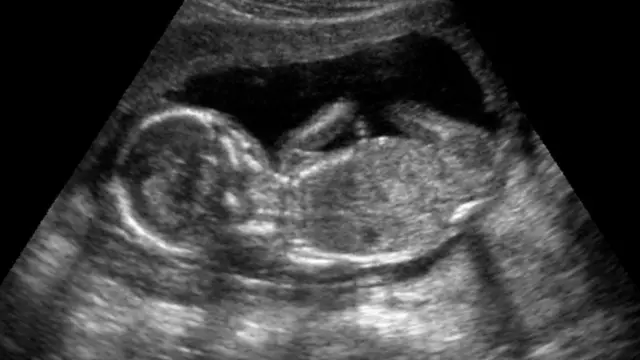

Donde la situación se complica particularmente es si la víctima está embarazada.

En estos casos, la familia del paciente está ante una elección desgarradora. Pueden aceptar que han perdido a su bebé por nacer, o comenzar la intensa y a menudo espantosa batalla para mantener a la madre el tiempo suficiente hasta el parto, lo que ocurre generalmente cuando el feto tiene aproximadamente 24 semanas.

El forcejeo entre los intereses de la madre y los de su bebé por nacer plantea la pregunta: ¿qué derechos humanos debemos retener cuando estamos muertos?